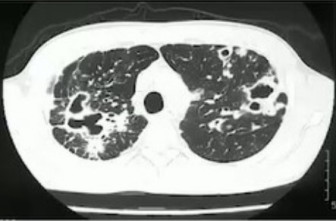

みなさんは「非結核性抗酸菌」というものを聞いたことがあるでしょうか?「抗酸菌」とは酸性アルコールによる脱色に抵抗性を持つ細菌の総称であり「結核菌」や「らい菌」(ハンセン病)がその代表です。そしてそれ以外の「抗酸菌」を「非結核性抗酸菌」(NTMnontuberculous mycobacteria)と呼びますが、近年の日本では肺結核が減少する一方で、肺NTM症が増加の一途を辿り問題となっています。

NTM

はもともと土や水などの環境中にいる菌で、結核菌とは異なり人から人には感染しません。200以上もの菌種がありますが、人に感染して問題になるのは ①マイコバクテリウム・アビウム ②マイコバクテリウム・イントラセルラー ③マイコバクテリウム・カンサシー ④マイコバクテリウム・アブセッサスの4種類で、①と②を合わせたMACM. avium complex)と呼ばれる菌が肺NTM症の約90%を占めます。肺NTM症は中高年の女性に多い傾向にあり、慢性的な咳や痰、血痰、倦怠感、発熱、体重減少などがみられます。無症状の場合も多く、胸部レントゲンの異常で発見されることもしばしばです。肺NTM症の確定診断には胸部CT、喀痰などの培養検査、血液によるMAC抗体測定が行われます。CTで空洞のないタイプ「結節・気管支拡張型」は5年生存率が8割以上ですが、空洞のあるタイプ「線維空洞型」では5年生存率が4割以下(治療により6割以上)と予後不良です。症状のない「結節・気管支拡張型」では経過観察となることが多く、有症状者や「線維空洞型」では治療が必要となります。標準治療としてマクロライド系の抗生物質(クラリスまたはジスロマック)+エタンブトール(+リファンピシン)の長期内服があり、空洞を有する症例やマクロライド耐性例ではアミノグリコシド系を併用します。治療効果として、喀痰培養でNTM陰性となるのは約47割であり、難治例には新薬のアミカシン吸入薬(ALISAMKリポソーム吸入懸濁液)が用いられることもあります。またNTM症は再発率が4割以上と高く、喀痰培養でNTM陰性となった場合でも15ヶ月間はさらに内服継続をすることが望ましいとされます。今後はより効果が高く、より副作用の少ない新薬の開発が待たれます。